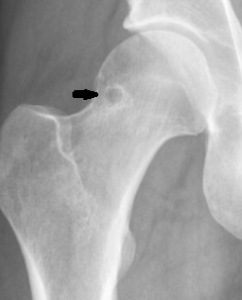

5. Synovial Herniation Pit

This non-pathologic radiolucency is seen in up to 5% of the adult population and is most often asymptomatic, though symptomatic cases have been described. The classic appearance is a round, ovoid, or “8-shaped” radiolucency with a thin sclerotic border most often found at the anterior superior femoral neck, though it can be found in the anterior inferior femoral neck as well. It is formed by a herniation of synovium through a cortical defect of the femoral neck. They are usually 5-mm or less in diameter and are more often found unilaterally than bilaterally.